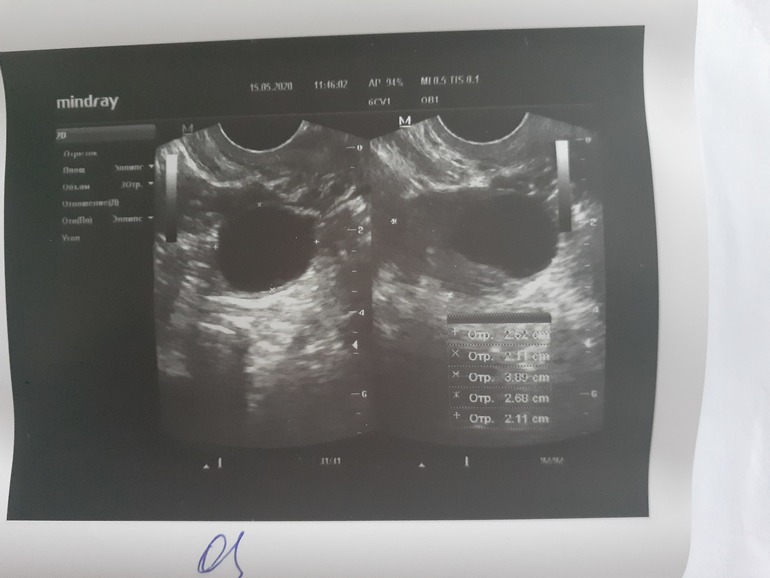

Девочки привет!!! Моя долгожданная беременность наступила и я очень счастлива 🥰 последние месячные 14 апреля, очень тянет низ живота справа, решила сходить на узи исключить вб, понимаю что рано, но очень переживала. По результатам узи в матке плодное яйцо 2.5 мм. Но жт четко не определяется! Сказали прийти через 3 недели повторно. У кого так было что жт не определялось или не было вообще? И благополучно ли завершилась беременность?

Врач узи сказала что вообще удивительно что она ПЯ увидела так как срок очень маленький! Я на дюфастоне пью 1 таб 2 раза в день.

Пя 10*14

Жм 3.80 так же это называется амниотическим мешком